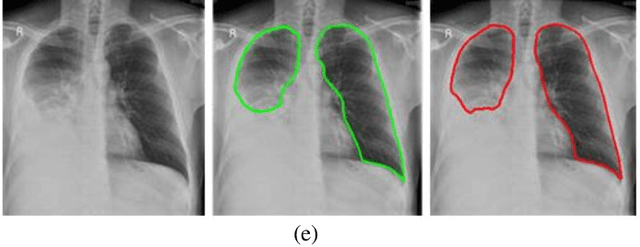

Abstract:A chest radiograph, commonly called chest x-ray (CxR), plays a vital role in the diagnosis of various lung diseases, such as lung cancer, tuberculosis, pneumonia, and many more. Automated segmentation of the lungs is an important step to design a computer-aided diagnostic tool for examination of a CxR. Precise lung segmentation is considered extremely challenging because of variance in the shape of the lung caused by health issues, age, and gender. The proposed work investigates the use of an efficient deep convolutional neural network for accurate segmentation of lungs from CxR. We attempt an end to end DeepLabv3+ network which integrates DeepLab architecture, encoder-decoder, and dilated convolution for semantic lung segmentation with fast training and high accuracy. We experimented with the different pre-trained base networks: Resnet18 and Mobilenetv2, associated with the Deeplabv3+ model for performance analysis. The proposed approach does not require any pre-processing technique on chest x-ray images before being fed to a neural network. Morphological operations were used to remove false positives that occurred during semantic segmentation. We construct a CxR dataset of the Indian population that contain healthy and unhealthy CxRs of clinically confirmed patients of tuberculosis, chronic obstructive pulmonary disease, interstitial lung disease, pleural effusion, and lung cancer. The proposed method is tested on 688 images of our Indian CxR dataset including images with severe abnormal findings to validate its robustness. We also experimented on commonly used benchmark datasets such as Japanese Society of Radiological Technology; Montgomery County, USA; and Shenzhen, China for state-of-the-art comparison. The performance of our method is tested against techniques described in the literature and achieved the highest accuracy for lung segmentation on Indian and public datasets.